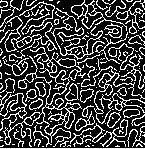

Segmentation:

The technique of segmenting an image involves breaking it up into several region, to detect objects or otherimportantdetailsindigital image.Therearemany edge detector in DIP Robert edge detector, Prewitt edge detector, sobel edge detector, canny edge detector and logedgedetectorshereinthisworkcannyedgedetector, is used for cancer cell detection since Canny edge detectorisbestforvisualappearance.

Canny edge detection is composed of five steps which areasfollows.

1. NoisereductionusingGaussianfilter 2. Gradientcalculation 3. Non-maximumsuppression 4. Doublethreshold 5. EdgeTrackingbyHysteresis

Fig5:Cannybasedimage